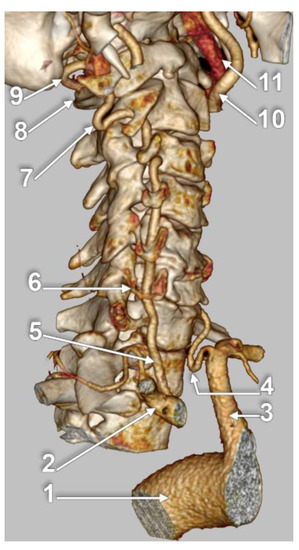

3.4. TF Entrance of the VA

3.5. Prevalence of the VA Course

3.5.1. Tortuosity

3.5.2. Straight V1 Segment Prevalence